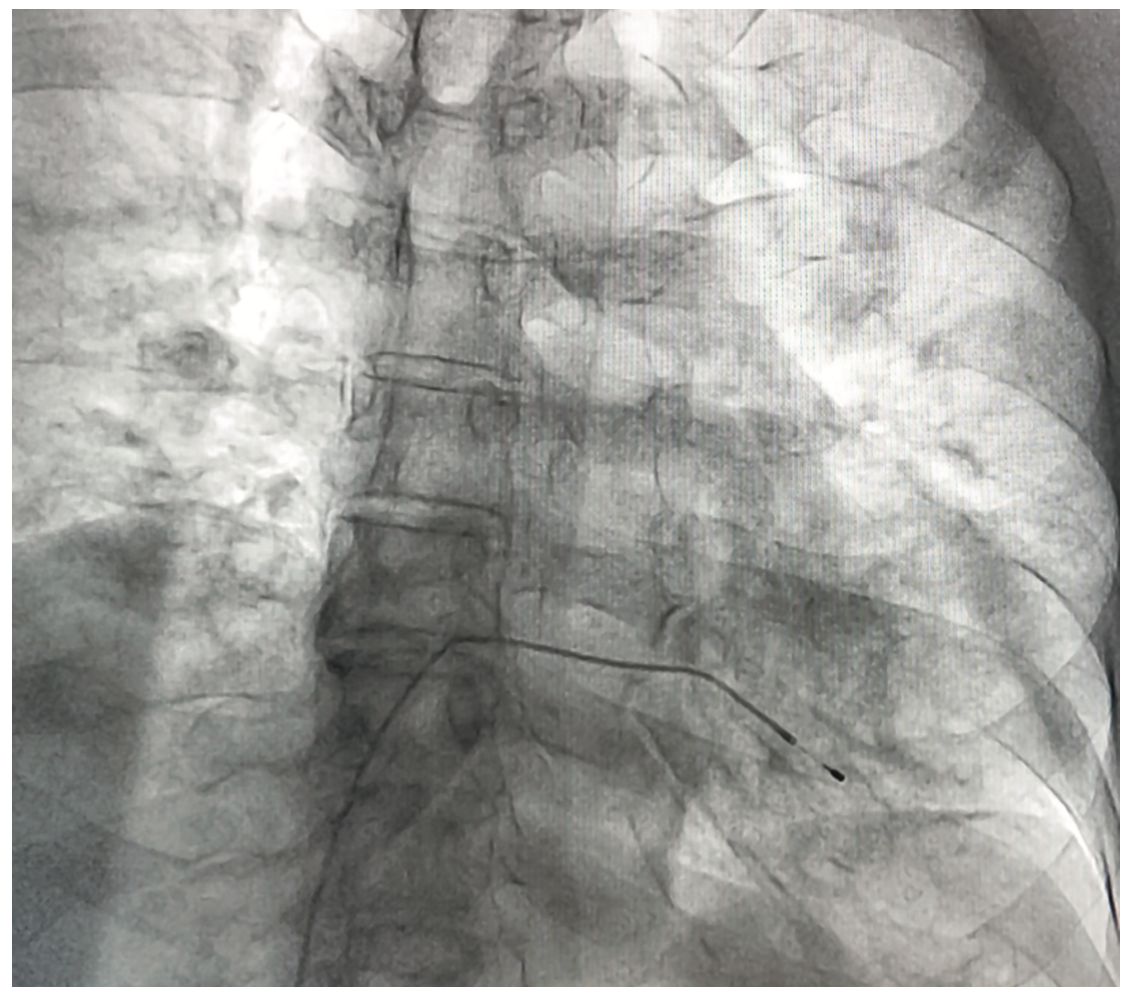

We report the case of a 77-year-old male who underwent temporary pacemaker lead implantation after a symptomatic 2:1 Mobitz type II second-degree block and left bundle branch block conduction (Figure 1). The temporary pacemaker was implanted apparently through the right jugular vein without fluoroscopic guidance, only by monitor guidance. After medical stabilization the patient was referred to our tertiary care center for further management. A cardiovascular system examination was unremarkable. Electrocardiogram showed a paced left bundle branch block pattern; however, with a high threshold stimulation level. The x-ray showed an abnormal lead path (Figure 2). A computed tomography angiography was performed that documented an intra-arterial lead with entry into the right common carotid artery and with the tip crossing the aortic valve and ending in the left ventricular outflow tract (Figure 3). Removal of the lead and relocation of the temporary pacemaker was requested by interventional cardiology. The fluoroscopy showed a temporary pacemaker lead with an arterial course with a loop in the ascending aorta and the tip crossing the aortic valve (Figure 4). A puncture of the right common femoral vein was performed, and a 6 French introducer sheath was placed. The temporary pacemaker lead was advanced to the right ventricle (Figure 5). The intra-arterial lead was removed and an angiogram was performed through the introducer sheath, confirming the arterial site (Figure 6). The introducer sheath was subsequently removed without complications.

In this case, the temporary pacemaker lead was unintentionally malpositioned through arterial access, suspected due to a high threshold stimulation level. An x-ray and computed tomography scan confirmed an abnormal lead path.